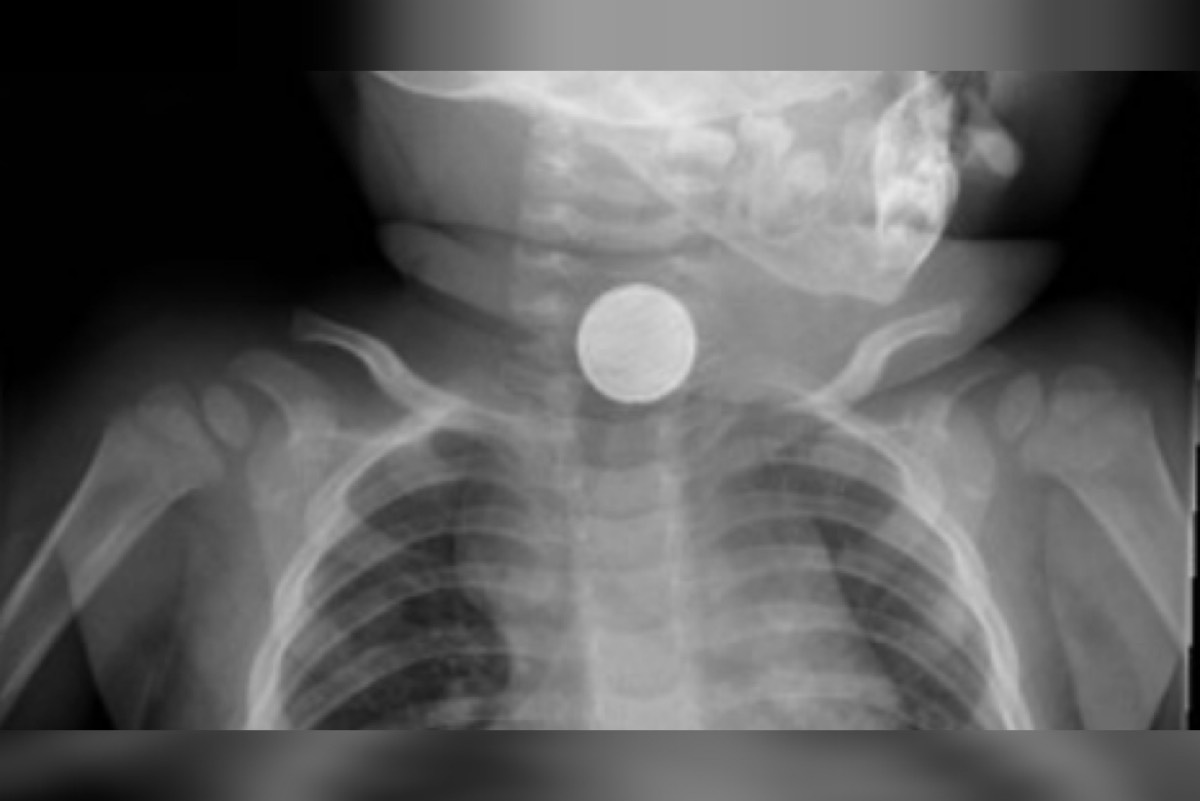

وقالت الصحة السعودية أن الطفل نقل لمستشفى بيشة للولادة والأطفال وهو يعاني من وجود جسم غريب في المريء أدى إلى صعوبة في البلع والتنفس. وبعد عمل الفحوصات السريرية والإشاعية تبيّن وجود بطارية محشورة بالمريء ليتم على الفور إدخاله لغرفة العمليات واستخراجها بالمنظار وبدقة عالية دون حدوث أي مضاعفات.

وأكد الفريق الطبي أن هذه العمليات تعمل بحذر شديد تحسباً لانفجار البطاريات داخل التجويف مما قد تتسبب بحدوث حروق كيميائية ومضاعفات مميتة.